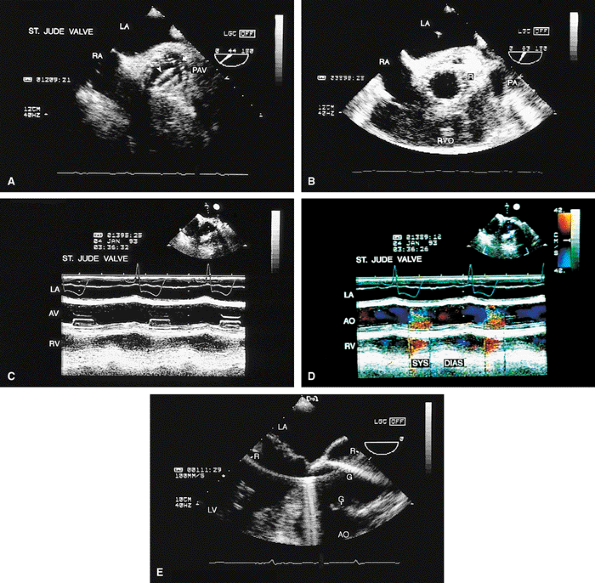

FIGURE 5.31. CarboMedics aortic prosthesis: paravalvular regurgitation. A,B. The aortic regurgitation (AR) jet occupies essentially the entire left ventricular outflow tract (LVOT) proximally, indicative of severe regurgitation. In both A and B, the most proximal portion of the AR jet is not imaged because of acoustic shadowing (S) caused by the metallic prosthesis (P), calcification, or both. AO, aorta; RPA, right pulmonary artery; RVO, right ventricular outflow tract. |